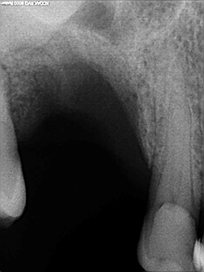

Le comblement alvéolaire est une technique de chirurgie pré-implantaire visant à anticiper la résorption osseuse consécutive à une extraction dentaire, dont elle est en principe concomitante.

Une fois la dent extraite, un greffon est mis en place dans l’alvéole (ancien « trou » dans lequel se trouvait la dent absente) et recouvert d’une membrane type collagène pour assurer la prise de la greffe.

Le bon comblement alvéolaire dentaire est vérifié au bout de quelques mois par imagerie médicale type cone-beam. Puis la pose classique de l’implant peut être réalisée.